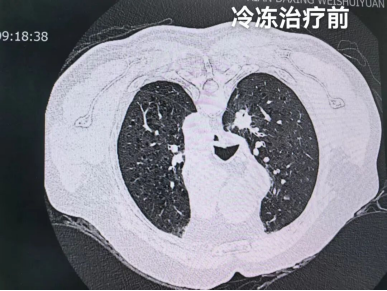

治疗流程按预设方案有序推进:第一步为CT引导精准定位,在影像科团队的协助下,医生借助CT影像系统清晰标定左肺结节的三维坐标,精准锁定病灶范围,为后续操作建立精准导航。

整个治疗过程耗时约1.5小时,顺利完成。术后即时影像检查显示,肿瘤病灶已被冰球完整覆盖,消融效果达到预期。